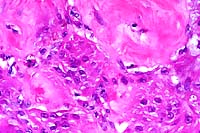

10x

obj

- Case 20-1. Bone. The necrotic bone (right), and marrow

is being replaced by neutrophils, macrophages and fibroblasts

forming collagen (center & left).